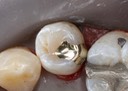

Joe Cha #19 pre-op

Joe Cha #18 pre-op